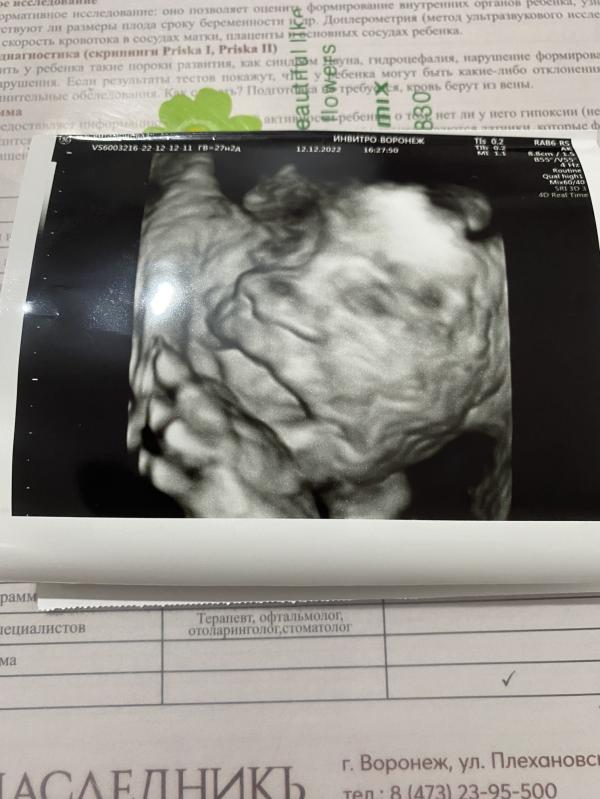

Это уже третья беременность, третья девочка, но все равно, так удивительно смотреть на узи, как ребеночек в МОЕМ 😄 животе, открывает ротик и сосет кулачок🥰

Стоит однозначно в 23 недели ходила, вообще супер! Мега эмоции! Прям лялька в животе. А с мужем пошли в 33 уже практически ничего не увидели, только частями.

В Олимпе здоровья записывают на флэшку,но платно.в медэесперте бесплатно в лк остаётся.но вот интереснее всего видео на 2 скрининге,а 3 уже слишком большие и так хорошо все не разглядишь/не запишешь